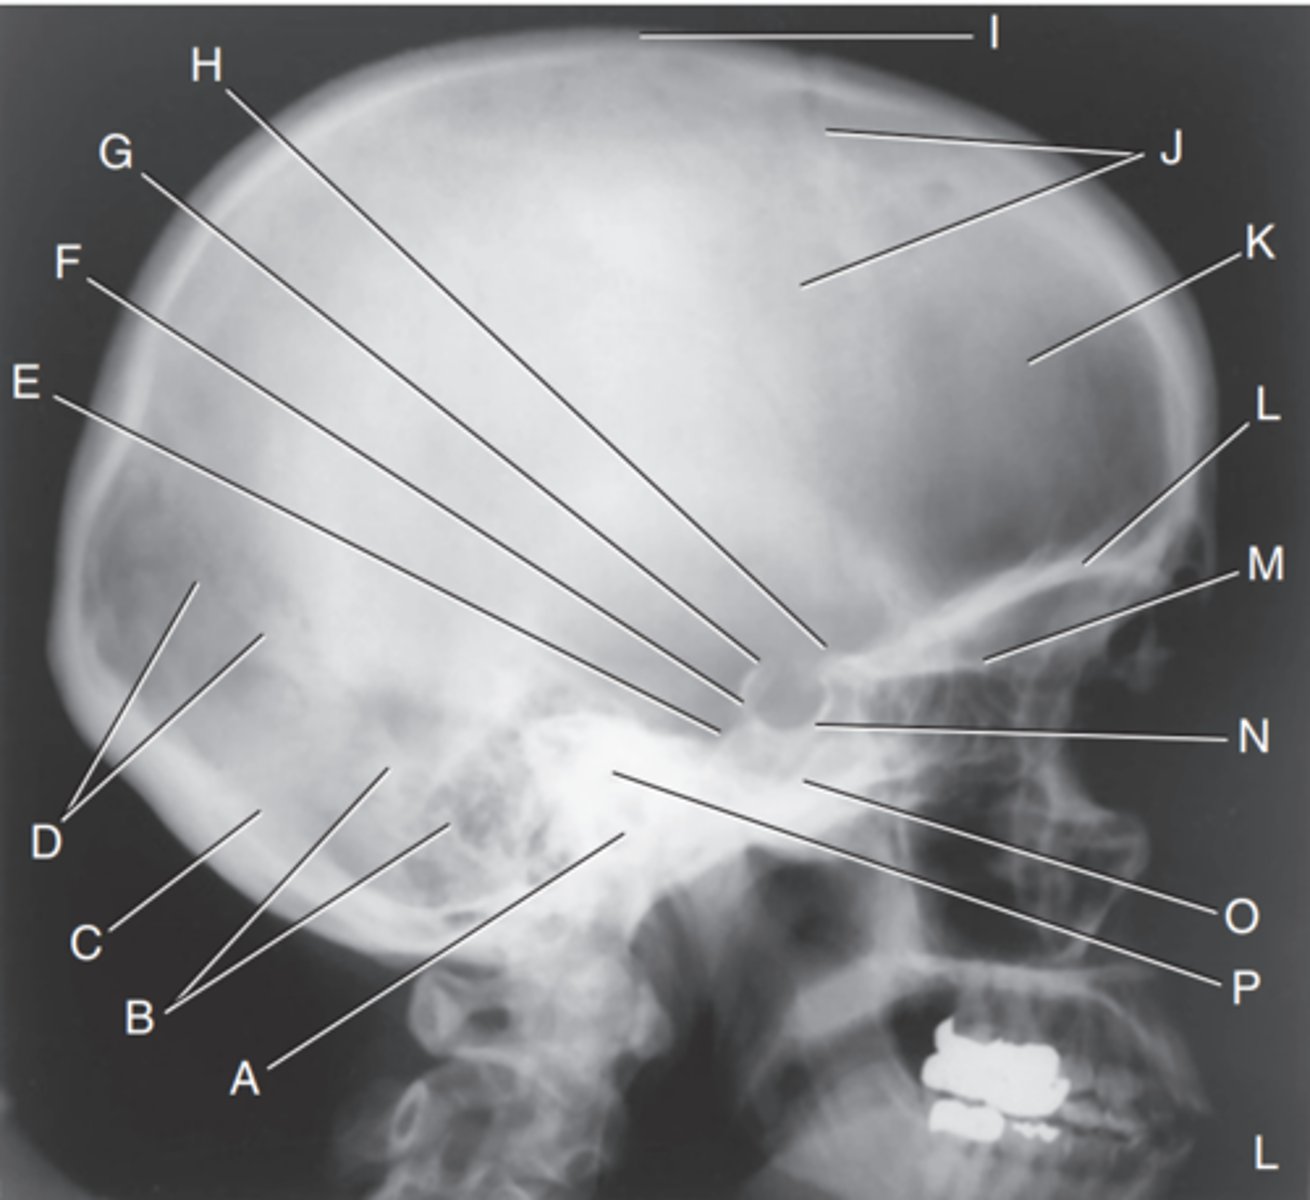

EAM

Label A

Mastoid portion of temporal bone

Label B

Occipital bone

Label C

Lambdoidal suture

Label D

Clivus

Label E

Dorsum sellae

Label F

Posterior clinoid processes

Label G

Anterior clinoid processes

Label H

Vertex of cranium

Label I

Coronal suture

Label J

Frontal bone

Label K

Orbital plates

label L

Cribriform plate

Label M

Sella turcica

Label N

Body of sphenoid (sphenoid sinus)

Label O

Petrous portion of temporal bone

Label P